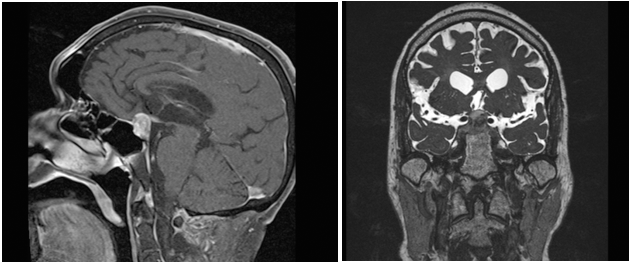

Three months later the patient presented acutely with complaints of headache, nausea/vomiting, altered mental status and diplopia. Physical examination revealed bitemporalhemianopsia and CNIII palsy. Laboratory and imaging workup revealed panhypopituitarism and a 1.7cmx1.9cm contrast enhancing surpasellar hemorrhagic mass impinging on the optic chiasm with extension into the cavernous sinuses R>L (Figure 2). Treatment options were discussed and the patient chose to undergo surgery for resection of the macroadenoma. The patient successively underwent Endoscopic Endonasal Transphenoid Resection of the Pituitary Adenoma (Insert surgical protocol) (Figure 3). Post-operatively, the patient had no major complications or focal motor or sensory neurological deficits. Patient noticed immediate improvement in his peripheral vision with marked resolution of CN III palsy several days post-op. Patient had no complications, clear rhinorrhea, or infection. Patient was placed on hormone replacement therapy (with Hydrocortisone, Synthroid and Vasopressin) due to his panhypopituitarism from pituitary apoplexy.

Figure 2 A) Pre-Gamma Knife T1 Weighed MRI (Sagittal View); B) Pre-Gamma Knife T1 Weighed MRI (Coronal View).